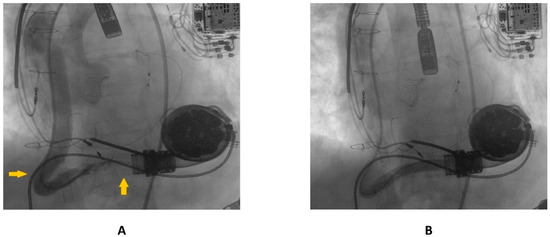

The first guidewire was removed and a 0.035″ × 260 cm stiff guidewire (Amplatz Super Stiff™, Boston Scientific, Natick, MA, USA) was deployed distally. Following this, an “anchoring technique” [8] with a 12 mm balloon located in the proximal tract of the outflow graft was adopted in order to advance the long sheet throughout the kinking. After that, a balloon-expandable 10 × 79 mm endoprosthesis (GORE® Viabahn® VBX) was implanted. Distal anchoring and stent positioning are shown in Figure 3A,B.

Figure 3.

(A) distal anchoring; (B) stent deployment.

Due to severe underexpansion of the implanted stent, several postdilations were performed using peripheral balloons of increasing diameters (MUSTANGTM 0.035″, Boston Scientific) (see Figure 4).

Figure 4.

Postdilation of the implanted stent.